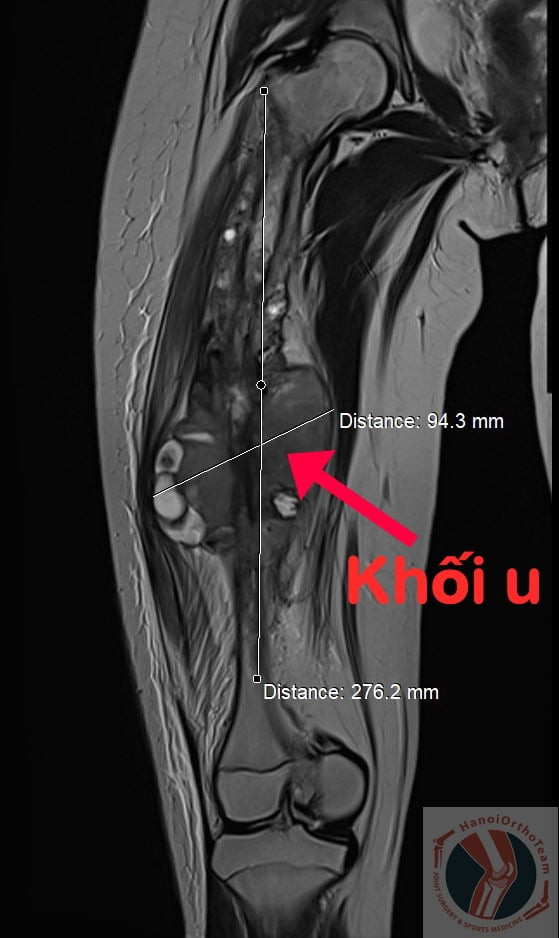

Hình ảnh khối u khổng lồ phá hủy gần toàn bộ xương đùi phải của bệnh nhân.

Đối với trường hợp cháu Q.A, khối u đã phát triển quá mức dọc theo thân xương đùi và xâm lấn “ăn” gãy đôi thân xương. Do đó, giải pháp duy nhất là phải tháo bỏ toàn bộ xương đùi kèm theo khối u. Nhưng nếu không có giải pháp thay thế vị trí khuyết của xương thì nguy cơ phải cắt bỏ chân của cháu để cứu tính mạng là rất cao! Tuy nhiên, do cháu còn quá nhỏ và gia đình cũng khát khao đặt nhiều niềm tin vào việc bảo tồn chân cho con nên các bác sĩ đã tìm ra một giải pháp phù hợp nhất cho cháu.